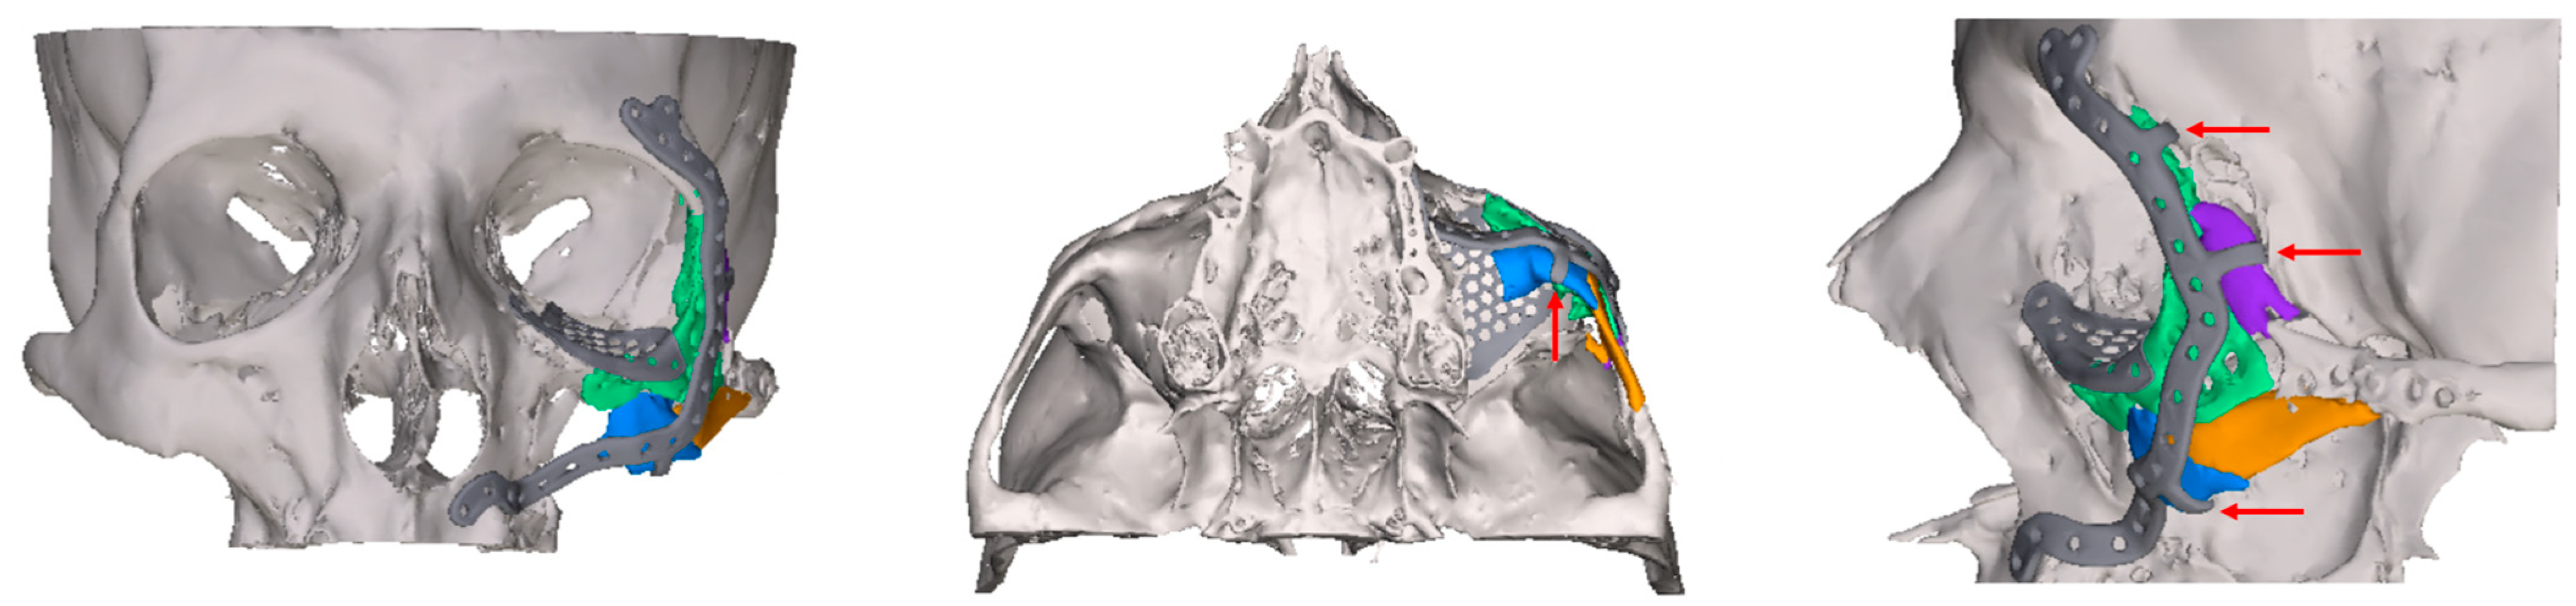

2.2. Digital Workflow and Implants

- Exposure of the fixation screws (infraorbital recess of the maxillary sinus) and limited exposure of the PSI (transition zone, ethmoid cells) without signs of mucosal swelling in these regions (n = 6 each)

- Bone apposition at the PSI as a sign of osseointegration (n = 16)

- Remodeling of the dislocated bone fragments of the orbital walls (n = 16), including in the area of the infraorbital canal.